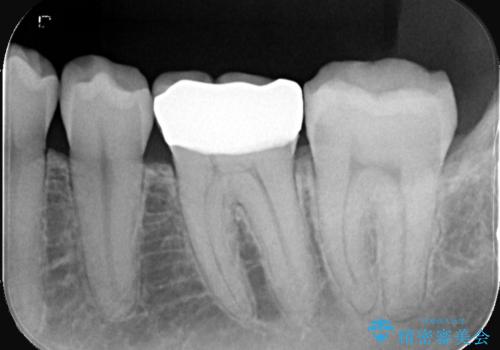

- 主訴:強く噛んだら歯がポロポロ欠けてきた。

左下6番目の歯の咬合面にプラスチックの材料が詰まっており、歯質がドーナツ状にしか残っていなかったため、歯質幅が比較的薄かった場所が欠けてしまったようでした。

今後の破折リスクを説明し、セラミッククラウンでのやり替えとなりました。

頬舌的レジンインレーが入っており、歯質幅の薄かった且つ強く咬合していた遠心側歯質が欠けてしまっていました。また新しい窩洞のインレーを入れても、近心側歯質の破折のリスクは抱えたままになることから、クラウンでの修復をおすすめし審美性・適合性のよいセラミッククラウンでのやり替えとなりました。